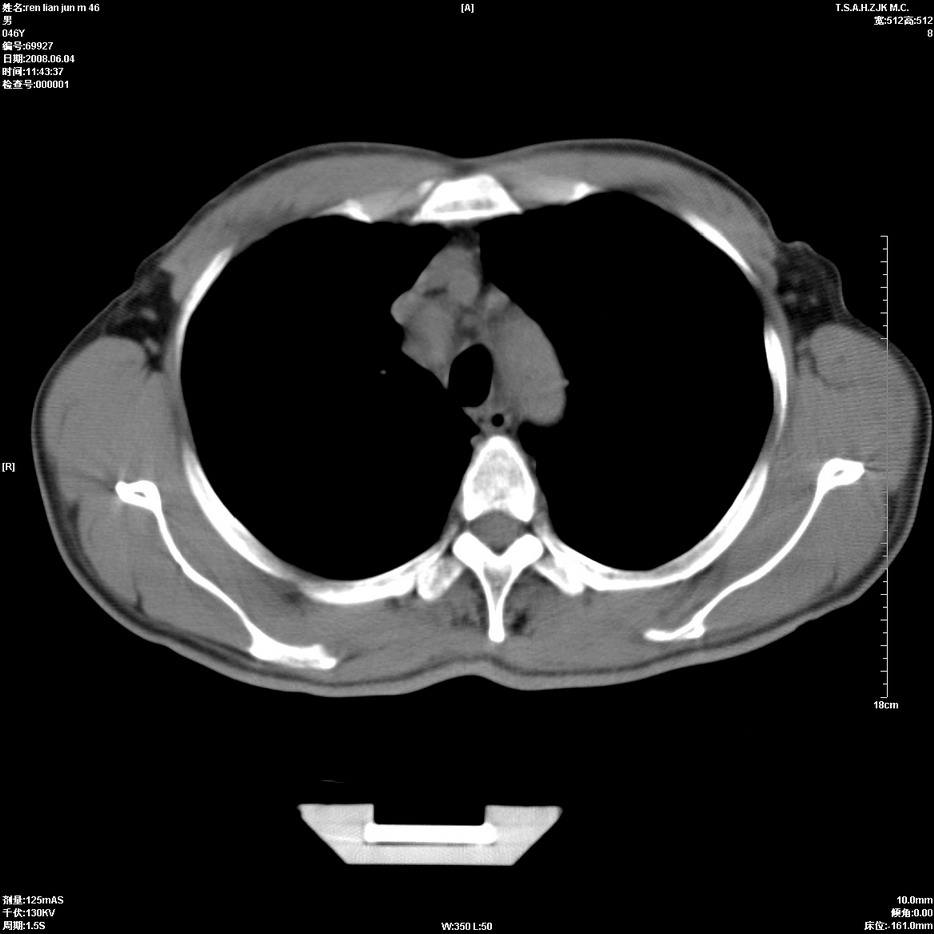

以下是引用qiu999在2008-6-5 17:14:00的发言:[br]考虑右肺中心型肺癌.颅内应做增强检查.

以下是引用形影不离在2008-6-5 19:18:00的发言:[br]右肺中心型肺癌并纵隔及左侧腋窝淋巴结转移,颅内应做增强检查。

以下是引用杀毒软件在2008-6-5 18:33:00的发言:[br]支持考虑右肺中心型肺癌,颅内病变是不是转移,不好说